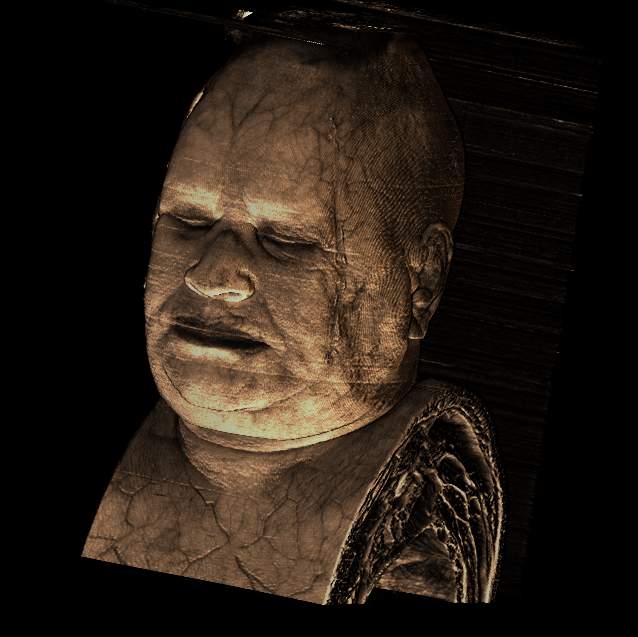

Visible human female MRI data

Shaded

head with skin

Data Resolution : 256x512x512